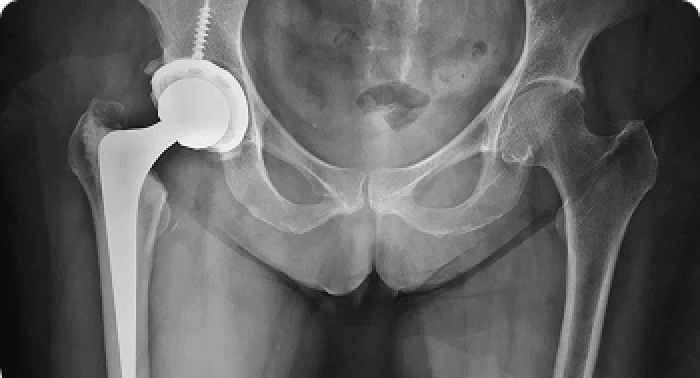

Prótese Total do Quadril

Para casos de artrose avançada ou necrose da cabeça femoral. Utilizo as próteses mais modernas, com técnicas que preservam músculos.

Quanto tempo dura uma prótese de quadril?

As próteses modernas têm alta durabilidade, geralmente entre 15 e 20 anos, podendo ultrapassar esse período com acompanhamento adequado. Fatores como peso corporal, tipo de atividade e qualidade do implante influenciam diretamente na longevidade. Consultas regulares com o especialista ajudam a monitorar o funcionamento da prótese e garantir o melhor desempenho a longo prazo.